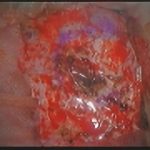

手術前2

摘出 中